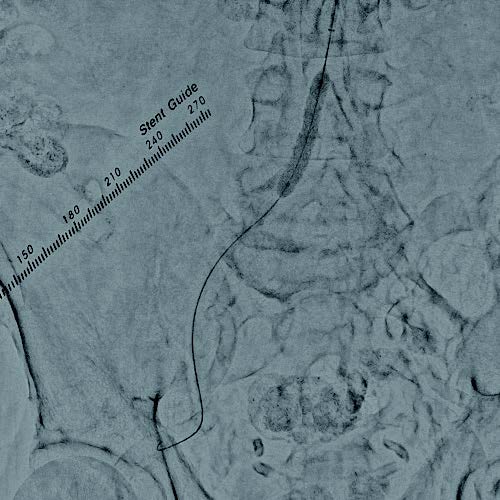

本症例は総大腿動脈からの順行性穿刺による右膝下動脈の治療を予定していることから、上腕動脈穿刺による腸骨動脈へのEVTを計画した。右上腕動脈から6 Frガイディングシースを用いてアプローチし、術前の下肢血管造影を行った。重症下肢虚血患者であり、安定したinflowの確保が重要と考え、高度石灰化を伴うことおよび血管径が11 mmと大きいことを踏まえ、後拡張の汎用性の高いVBX ステントグラフトを選択する方針とした。0.014 inchガイドワイヤーで病変通過後、6.0 × 40 mmバルーンで前拡張を行った(図1)。ガイドワイヤーを0.035 inchスティッフタイプに変更し、VBX ステントグラフト7 × 39 mmを後拡張での短縮を考慮し、数 mm 程度大動脈に突出させる形で留置した(図 2)。10.0 × 40 mmバルーンで後拡張(図3)を行い、IVUSで解離等がないことを確認し、最終造影で合併症が無いことを確認し手技を終了した。